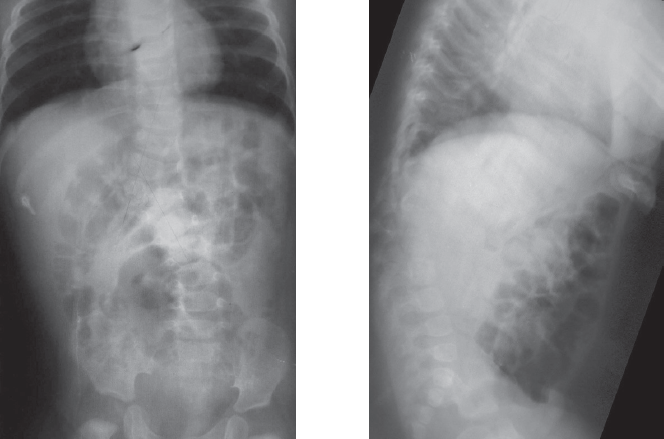

Clinical case of surgical treatment of advanced congenital kyphoscoliosis in 12 years old child is reported. Radiographs and CT at presentation failed to reveal the entire anomaly. By analysis of priorly made radiographs hemivertebra L1 was recognized. At genitourinary assessment L-shaped kidney was detected. A full-size 3D-printed model was used for surgical planning. Vertebral column resection as treatment option was discussed, but due to high neurologic complication rate this approach was refused. After preoperative 35 days halo-femoral traction anterior instrumented fusion was performed. Right ureter was stented for intraoperative urologic injury prevention. Scoliosis correction of 32% and kyphosis of 14% was achieved. 5 months later definitive posterior uninstrumented fusion was performed. Spinal deformities caused by vertebral malformations progress dramatically unless they are treated early. An advanced case is a clinical challenge because of technical difficulties and poor result. Vertebral column resection is a treatment option for severe kyphoscoliosis, but it’s indications should be strictly individualized. Preoperative halo-femoral traction is the most safe correction method in spinal deformity due to prolonged and gradual action. 3d-printed models are practical for surgical planning. The model may be used intraoperatively as a 3D-reference. In congenital scoliosis genitourinary system should be assessed meticulously, and urologist advice in relevant case is necessary.